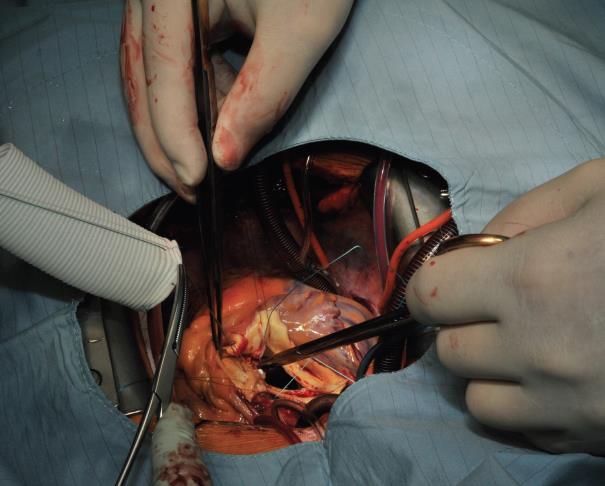

The procedure starts with the proximal suture of the composite graft prosthesis to the aortic annulus using separated mattress suture of 2.0 Ethibond backed with small Teflon pledgets. The first suture is placed at the level of the commissure between the left and right coronary sinuses and the following are stitched in a clockwise fashion (Image 1). The sutures are placed through the annulus with the pledgets left either on the aortic side thus everting the annulus, but in small annular diameters. The author prefers to stich these sutures from the ventricular side to the aorta, therefore the pledgets lie under the aortic annulus. Then the sutures are placed through the sewing ring of the composite graft prosthesis (Image 2) which is later on parachuted down to the aortic annulus (Image 3). The sutures are then tightened and the valve is placed into the outflow tract of the left ventricle (this provides excellent hemostasis).

Image 1: Suturing the composite graft to the aortic annulus starts at the level of the commissure between the left and right coronary sinuses and is continued clockwise in back-end fashion up to the middle of the non-coronary sinus. Thereafter fore-hand technique is applied for the rest of the non-coronary sinus and the left coronary sinus.